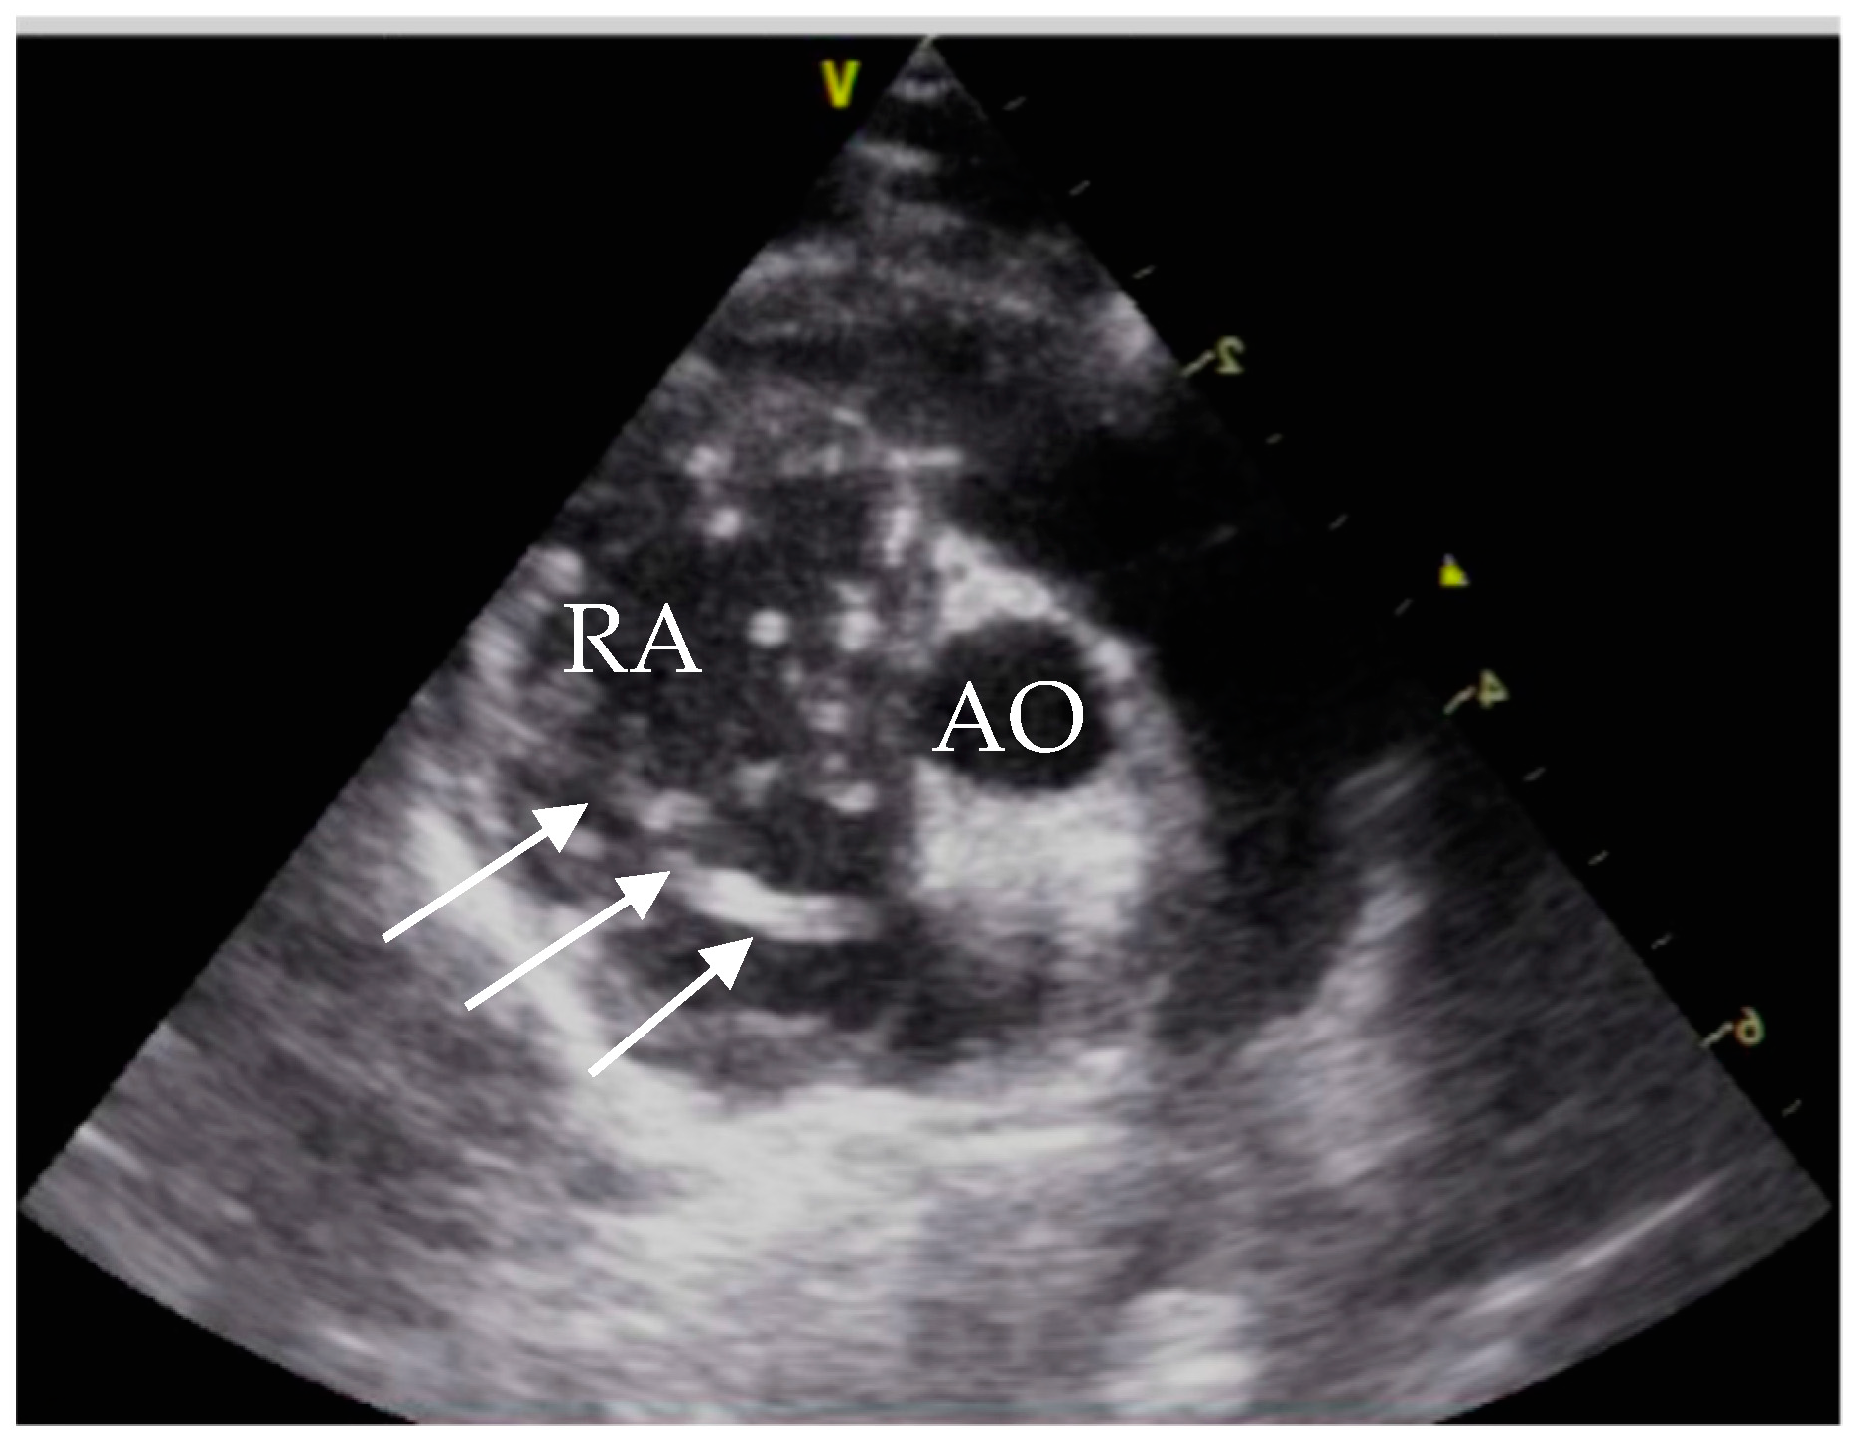

Additionally, an echocardiography was performed. The cat showed a tricuspid insufficiency (2.8 m/s), a mild mitral insufficiency and a pulmonary artery flow of Vmax 1.1 m/s (probably suggesting mild pulmonary hypertension). Comparing the two echocardiograms the cat’s hemodynamic status significantly improved (Table 2) with increased left ventricle preload. No heartworm was detectable (Figure 8). LA/Ao could not be measured in the initial echocardiography due to the enlarged right atrium.

Figure 8. Echocardiogram July 2021, right parasternal short axis view. RA = right atrium; RVOT = right ventricle outflow tract; AO = aorta; LA = left atrium; RPA = right pulmonary artery, LPA = left pulmonic artery.